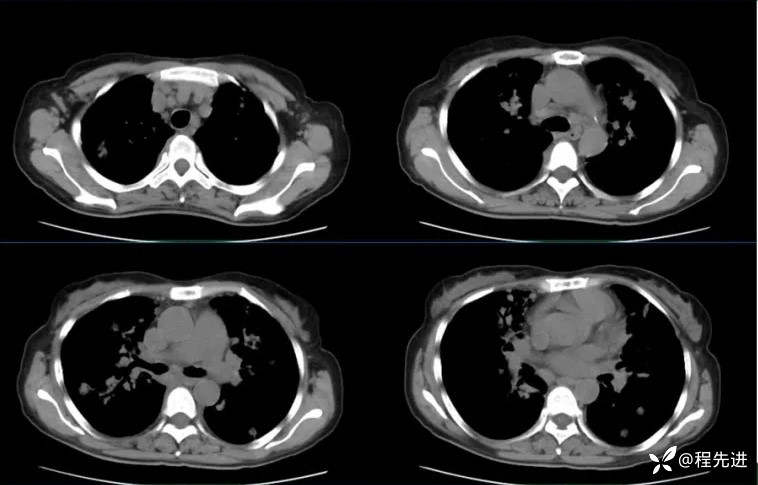

CT检查: